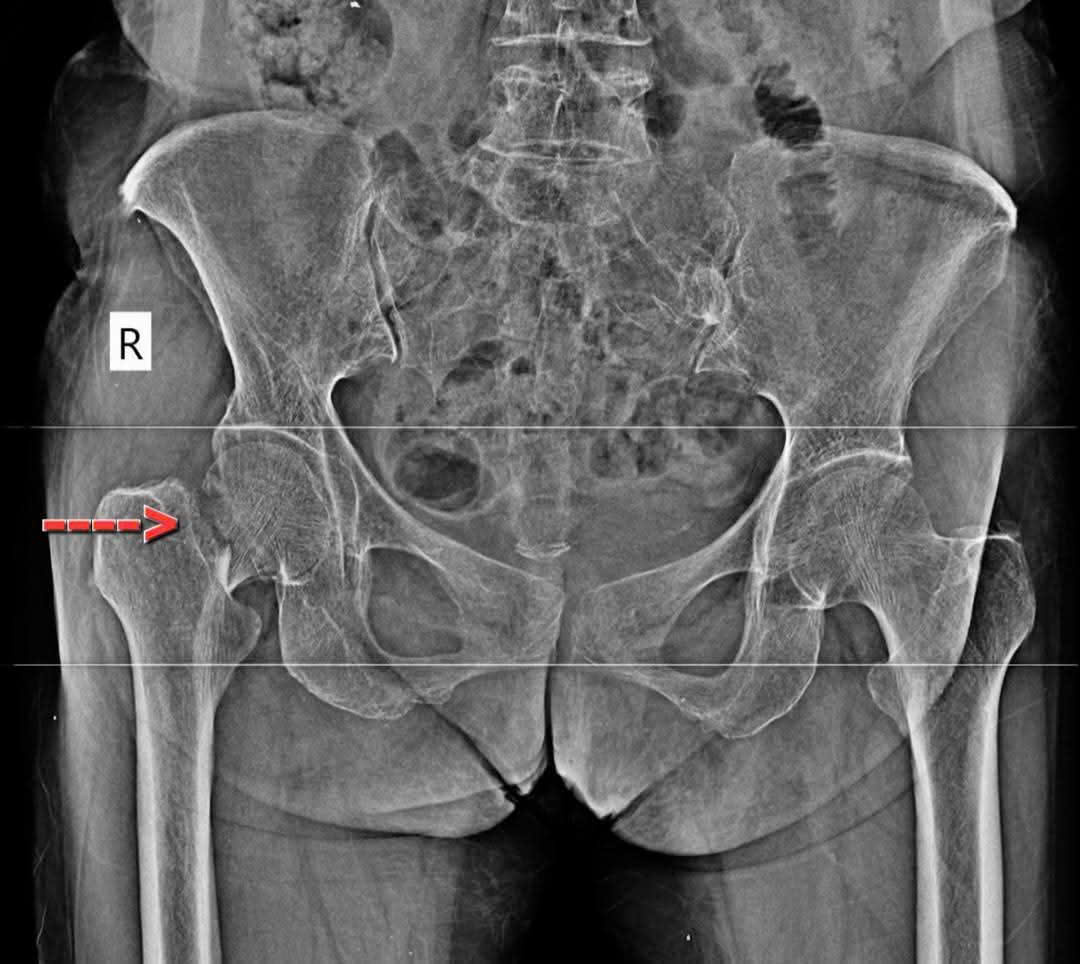

Gãy cổ xương đùi bên phải, Sau mổ thay khớp háng nhân tạo bán phần bên phải. Bệnh nhân bớt đau nhiều, có thể tự ngồi dậy sẽ tập đi lại trong vài ngày tới

Bệnh nhân nữ 74 tuổi gãy cổ xương đùi bên phải do té ngã và Sau mổ thay khớp háng nhân tạo bán phần bên phải. Bệnh nhân bớt đau nhiều, có thể tự ngồi dậy sẽ tập đi lại trong vài ngày tới